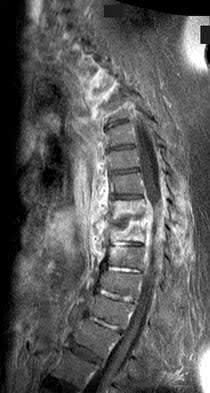

Figures 9a through 9c are the MRI scans of a 65-year-old woman on dialysis who has thoracic back pain, malaise, and an elevated erythrocyte sedimentation rate (ESR). The clinical history and imaging findings are most consistent with

The sagittal MRI scans are pathognomonic for diskitis and osteomyelitis with fluid signal and destructive changes in the disk on T2 (Figure 9a), low signal with blurring of the disk margins on T1 (Figure 9b), and on the T1 gadolinium image (Figure 9c) vertebral body enhancement on either side of the affected disk with dark signals within the disk corresponding to the bright fluid signal from the T2 image. Metastatic carcinoma tends to affect the vertebral body with relative disk sparing, and lymphoma can affect the vertebral body but often has soft tissue extending within the spinal canal. Osteoporotic fractures are contained with the vertebral body. Renal osteodystrophy can result in a diskitis picture with disk destruction but one would not expect an elevated ESR or malaise, and this is much rarer than diskitis in dialysis patients.